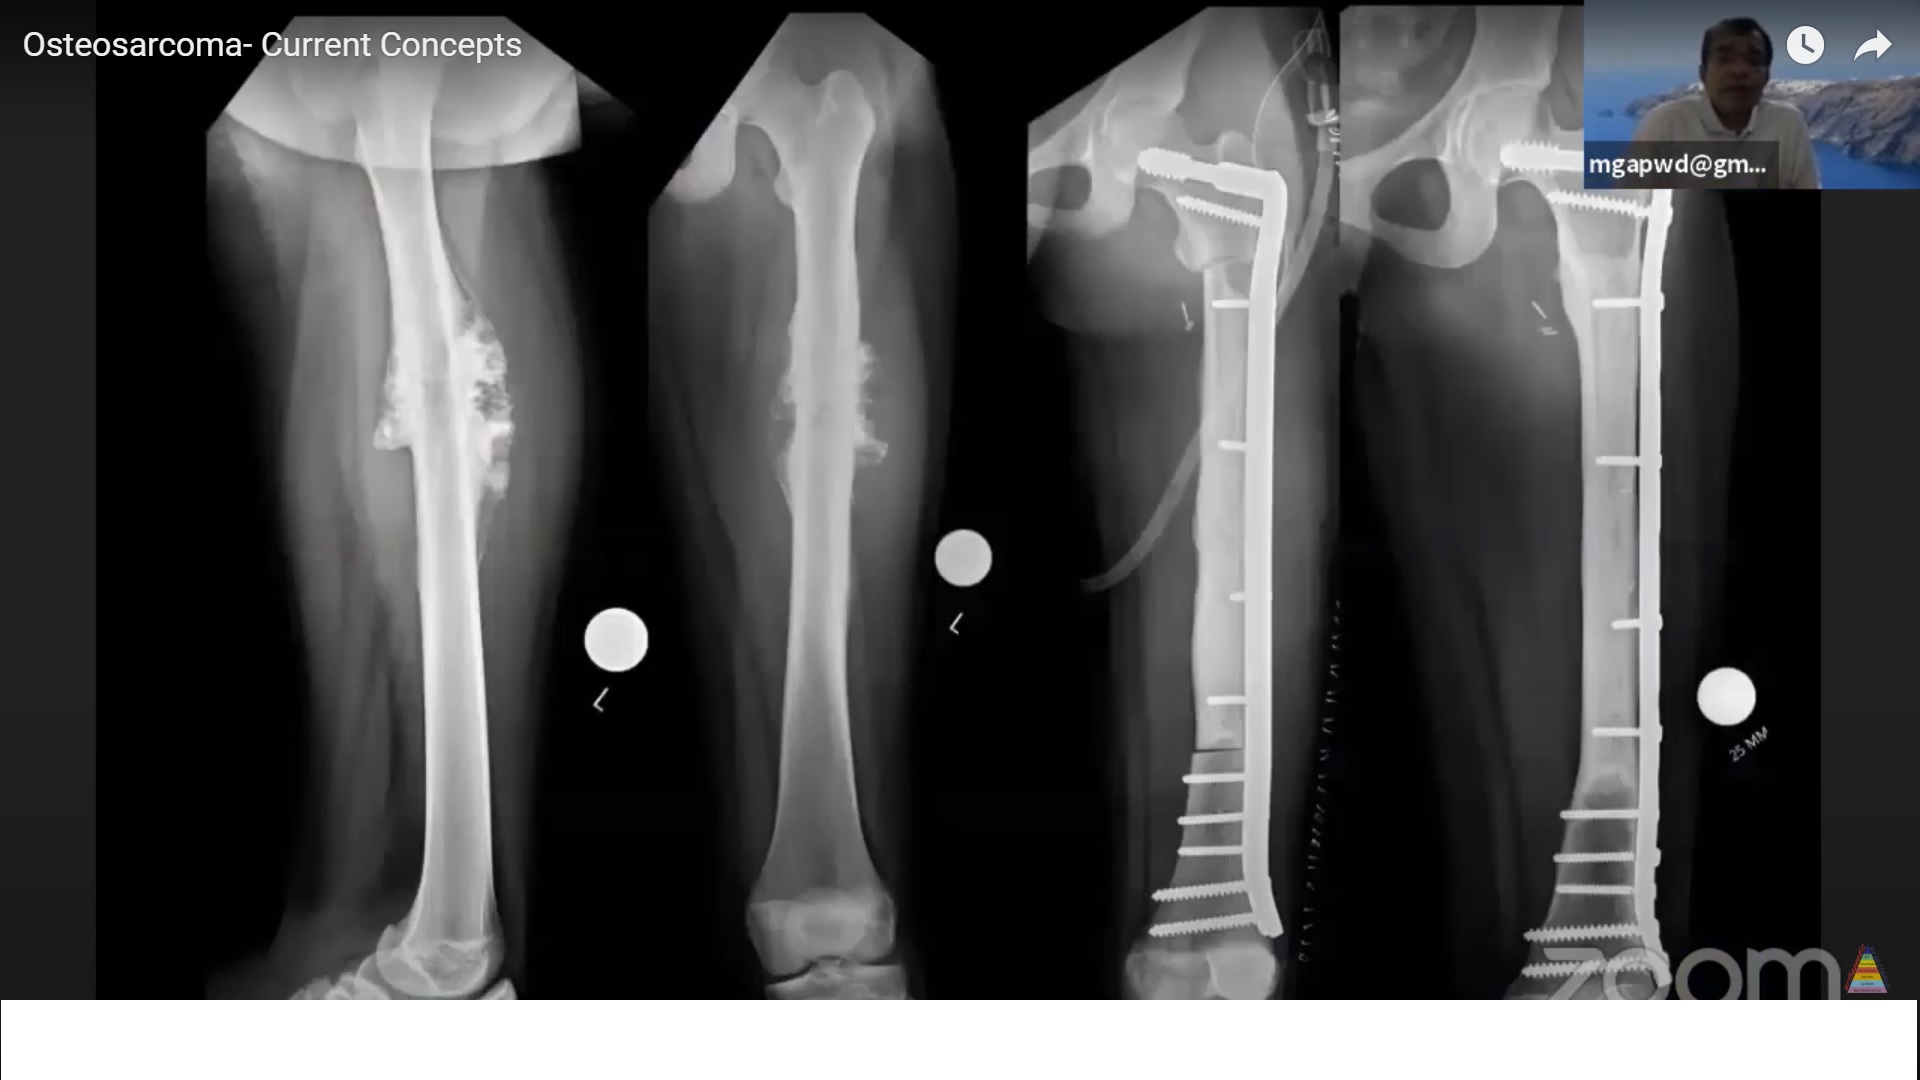

Radiographic Features (Plain Radiographs)

Aggressive metaphyseal lesion involving long bones.

May appear:

-

Blastic

Lytic

Mixed

Poorly defined, permeative margins.

Cortical destruction with an associated soft-tissue mass.

Treatment of High-Grade Osteosarcoma

Neoadjuvant chemotherapy

Wide or radical surgical resection or amputation

Adjuvant chemotherapy